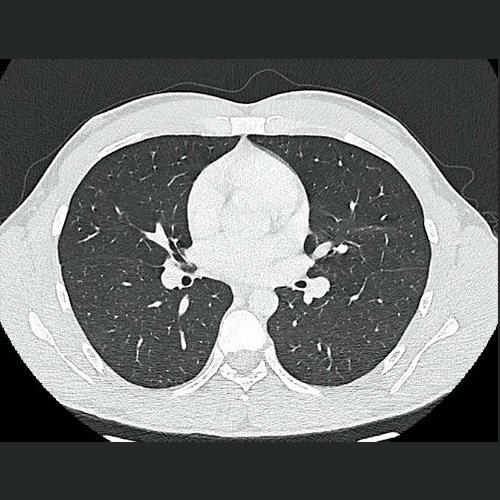

• TAC de Tórax (23/10/24): Escaso derrame pleural bilateral. No se visualiza imagen sugerente de Neumopatía.

TAC de tórax corte coronal y axial previas (23/10/24)